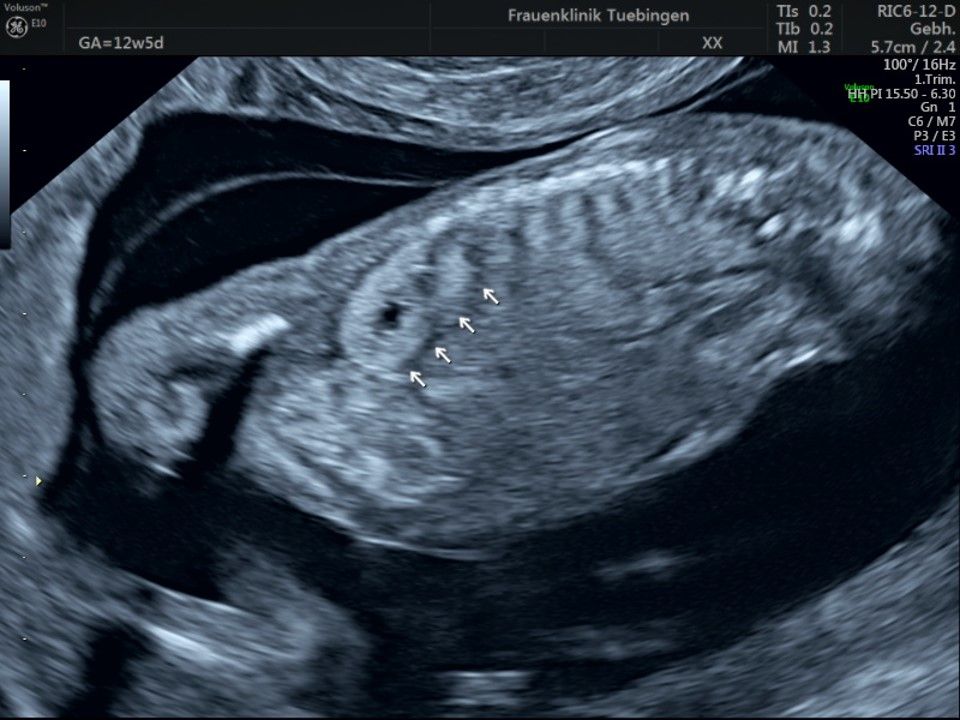

Im Rahmen des Ersttrimester-Screenings untersuchen wir die Organe des Feten mittels Ultraschall. Dabei machen wir auch gerne ein Bild für Sie.

Obwohl der Fet zu diesem Zeitpunkt erst zwischen 5 und 8cm groß ist, lassen sich bereits etwa die Hälfte aller schwerwiegenden Fehlbildungen erkennen bzw. ausschließen. Sollten wir eine Auffälligkeit sehen, werden wir mit Ihnen den Befund und das weitere Vorgehen ausführlich besprechen.

Das Ergebnis der Ultraschalluntersuchung ist wegweisend. Dabei wird der Fet vermessen, die Organe werden untersucht und die sonographischen Marker zur Risikoberechnung für Chromosomenstörungen werden beurteilt. Das sind: die Nackentransparenzdicke, Nasenbein sowie der Blutfluss in der rechten Herzhälfte und im Ductus venosus, einem Gefäß in der Leber des Feten.